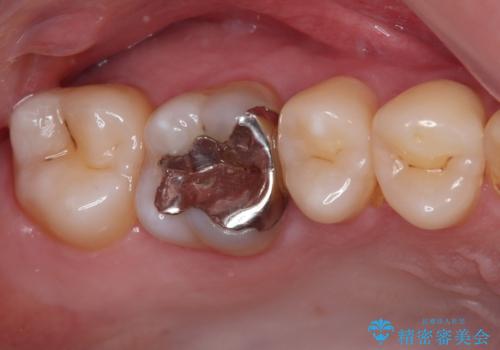

拡大鏡下で、銀歯、むし歯の除去を行い、セラミックインレーに適した形に整えました。

精度の良いインレーを製作するために、シリコーンにて型どりしました。

また確実な接着操作を行うために、インレーを接着する際にはラバーダム防湿を行いました。

- 21万円(税込) ※3歯費用は治療当時の料金となります